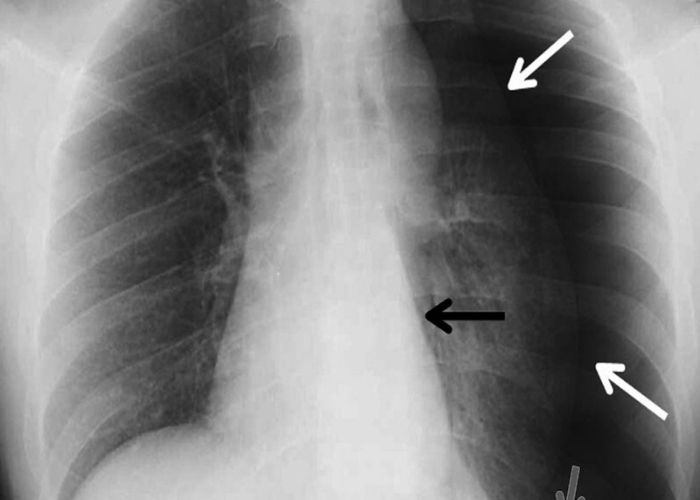

PLEVRAL EFFÜZYON

Akciğer zarı (plevra) akciğer ve göğüs duvarını örten iki adet zardan oluşmaktadır. Normalde bu iki zar arasında bir miktar sıvı bulunur ve emilim devam ettiği için birikim olmaz. Bu iki zar arasında akciğer kaynaklı ve akciğer dışı hastalıklarda metabolizmanın değişimi ile sıvı birikimi olur. Biriken bu sıvıya Plevral Effüzyon denir.

Plevral Sıvı Tanısı nasıl Konulur?

Fizik muayeneyi takiben Akciğer grafisi, Akciğer Tomografisi ile değerlendirilir. Torasentez(plevral sıvı örneklemesi), Bronkoskopi, VATS(Tek porttan) ve RATS ( ROBOTİK ) hem tanı hem tedavisi için uygulanan yöntemlerdir.